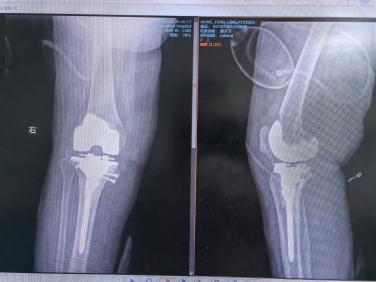

在武汉同济医院肖骏教授的指导下,通用技术湖北航天医院骨科主任黄飞团队精心规划,王女士的膝关节置换手术顺利完成。考虑到她的类风湿病史,医生团队制定了个性化的手术方案,使用微创技术进行精准的关节置换,最大限度减少术后并发症的风险。同时,术后制定了针对性的抗炎治疗和康复方案,确保她能够顺利恢复功能。

膝关节置换术后

术后仅一周,王女士便能够借助助行器下床活动,脸上重现久违的笑容,生活质量显著提升。